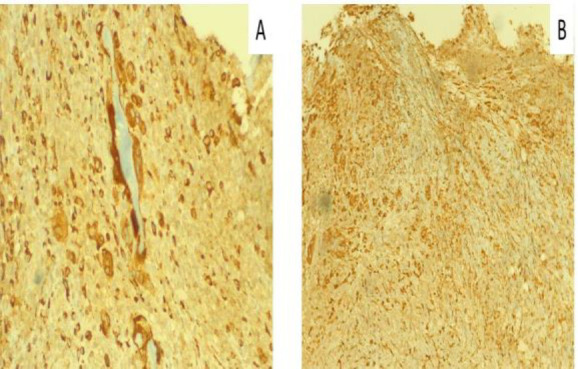

Case report: We report the case of a woman in her 70s, who was previously tracheostomized at another facility and was presented to our attention with glottic-subglottic stenosis. We performed a lysis of glottic synechia and subglottic debulking via transoral laser microsurgery, yielding satisfactory results over the short term. However, a relapse occurred within two months, along with ulcerative lesions on the nasal septum. Biopsies revealed multinucleated giant cells and inflammation suggestive of vasculitis. Based on the histological and clinical features, a diagnosis of vasculitis was considered. Anti-Neutrophil Cytoplasmic Antibodies testing was positive. A rheumatological examination confirmed the hypothesis of Granulomatosis with Polyangiitis. The lack of typical symptoms was the main reason for the delayed diagnosis.